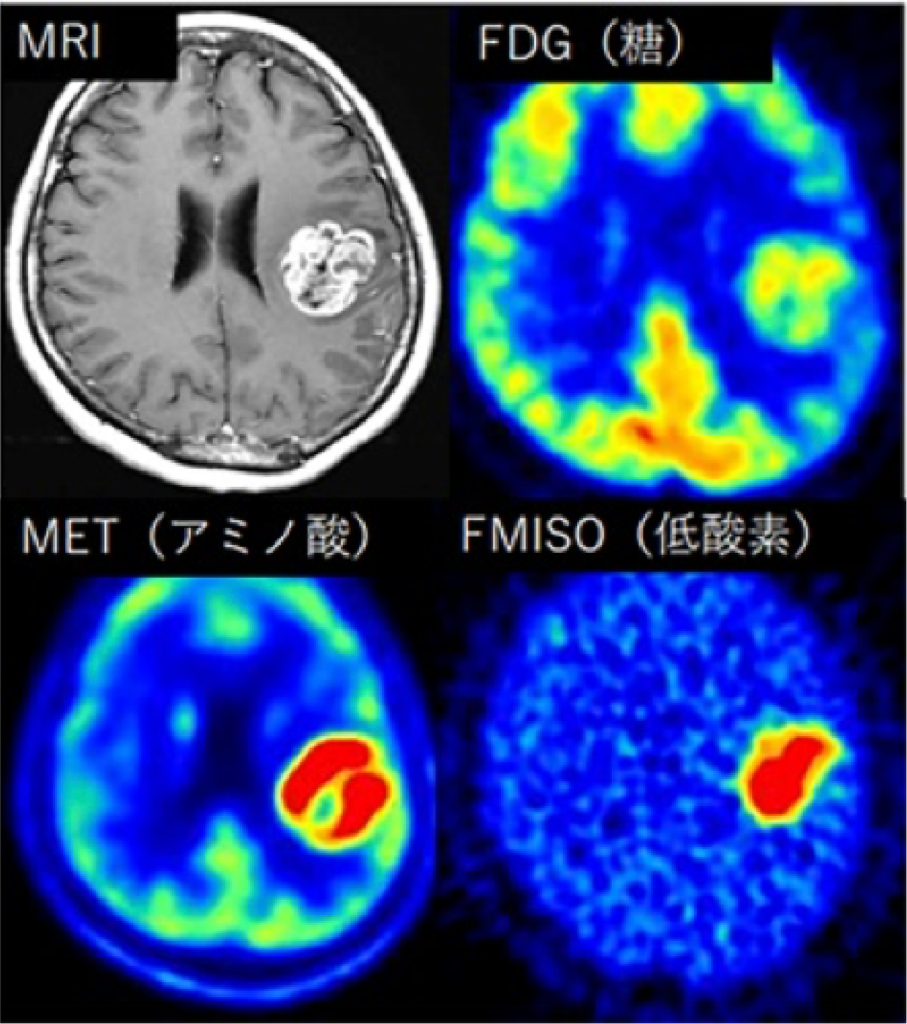

脳腫瘍のPET所見の分子生物学的検証

脳腫瘍診断はMRIを用いて行うことが一般的ですが、 当院では代謝イメージングであるPET(ポジトロン断層撮影法)を積極的に併用しています(図)。 腫瘍内の糖代謝、アミノ酸代謝、低酸素状態等を可視化できる診断方法ですが、 基礎研究ではこれらの診断で得られた情報と、手術で得られた腫瘍検体を組み合わせて分子生物学的な解析を行っています。 この研究から、予後予測につながる分子マーカーの発見、治療標的分子、腫瘍代謝メカニズムなどの解明を目指しています。